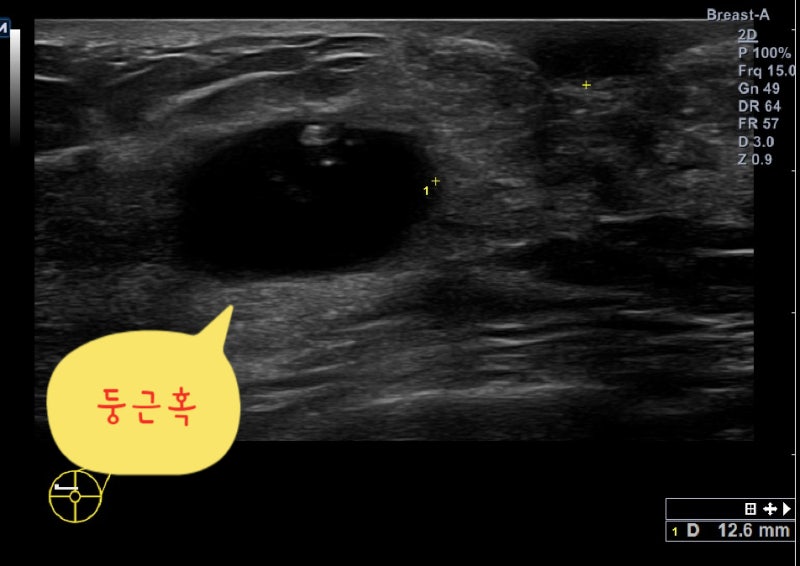

초기 유방암, 즉 1기 이하의 유방암은(겨드랑이 전이 없이 2cm 이하의 유방암) 만져지기 어려운 경우가 많습니다. 매년 유방 촬영과 유방 초음파 검사를 하지 않으면 초기에 유방암을 진단할 수 없습니다.유방 촬영술은 미세 석회화를 진단하는 데 좋은 검사 방법입니다. 미세 석회화만의 경우는 0기 유방암 또는 1기 유방암 소견입니다.유방 초음파 검사는 유방의 응어리를 진단하는 데 좋은 검사 방법입니다. 1기 이상 유방암은 대부분 유방 초음파 검사에서 응어리로 진단됩니다.

유방촬영술로 군집한 미세석회화 소견을 볼 수 있습니다. 0기 유방암 소견입니다.초기 유방암 사진유방 초음파 검사상 1cm 유방몽울입니다. 1기 유방암 진단을 받았습니다. 3 초기 유방암이 의심되는 응어리가 있을 때 조직검사유방에 혹이 진단되어 유방암인지 양성종양인지 정확한 진단이 필요한 경우 먼저 침총조직검사를 실시하십시오.젖클리닉위드심의원유방에 혹이 진단되어 유방암인지 양성종양인지 정확한 진단이 필요한 경우 먼저 침총조직검사를 실시하십시오.젖클리닉위드심의원유방침 총조직검사 동영상 접속 —> https://blog.naver.com/breastkim/221808987454유방몽울 총조직검사 <총생검> 과정 : 위드심 유방클리닉 김미혜 원장(전) 김미혜유 클리닉 원장 유방에 응어리가 진단되어 유방암인지 양성종양인지 정확한 진단이 필요하다면 먼저 침총조직검사를 해야함… blog.naver.com유방의 바늘 총 조직 검사 1. 유방 진료상 유방에 종괴이 진단되었습니다. 암입니까?유방 암의 대부분은 암이 아닌 양성 종양입니다.그러나 씨앗 덩어리 모양이 나쁘거나 크기가 커질 경우는 암을 의심하고 조직 검사를 해야 합니다. 2. 바늘 총 조직 검사는?<바늘 총 조직 검사>는 바늘을 유방 종괴에 넣어 일부 조직을 채취하는 조직 검사입니다.5개 이상의 조직을 채취해야 정확한 진단이 가능합니다.상처는 1mm정도로 거의 남지 않습니다.<바늘 총 조직 검사>는 전 세계적으로 널리 이루어지고 있는 유방 암 확진 방법으로 정확도는 99~100%입니다.3. 검사 방법 1) 누운 자세로 실시합니다.2)초음파 검사를 하면서 종륜 부위와 피부를 조금 부분 마취합니다3)바늘을 넣고 씨 덩어리에서 조직을 채취합니다. 조직을 채취할 때마다 “빵”소리가 납니다만, 통증은 없습니다. 5개 이상의 조직을 채취해야 하므로 5번 정도”빵”소리를 낼 있습니다.4)검사가 끝난 뒤 반창고나 붕대로 가슴을 닫습니다.4. 검사 시간 검사 시간은 5-10분에서 결과는 7일 이내에 전화로 알립니다.침총 조직 검사에서 꺼낸 유방 응어리 조직입니다.위 조직을 특수염색하여 현미경으로 조사하면 정확한 조직검사 결과가 나옵니다.섬유선종 특수염색 후 현미경 사진–>유방암 특수염색 후 현미경 사진 5. 검사 결과가 유방암으로 진단되면 대학병원으로 빠른 시일 내에 연결해 드리겠습니다.양성종양 진단 시 안심하셔도 되지만 *종양 크기가 큰 경우 *모양이 좋지 않은 경우 *사이즈가 커지는 종양*고위험 병변의 경우 <맘모톰 수술>을 권장합니다.유방암 진단을 받은 경우 빠른 시일 내에 대학병원으로 연계하여 치료받을 수 있도록 도와드리겠습니다.https://blog.naver.com/simjsmc/222505127069추악한 유방암에 대한 조직검사: 맘모톰 수술? 침총조직검사? : 분당위드심유방클리닉 못생긴 유방암에 대한 조직검사 : 맘모톰수술을 할까요? 침총 조직검사를 할까요? 안녕하세요 46살입니다… blog.naver.com4 초기 유방암이 의심되는 미세 석회화가 있을 때 유방조직검사미세 석회화가 모여 있을 때 <군집된 미세 석회화>라고 합니다. 이 소견의 20~30%가 0기 유방암일 수 있지만 나머지 70~80%는 양성으로 진단된다고 합니다.이를 정확하게 진단하기 위해 미세 석회화를 조직 검사하는 방법은 두 가지가 있습니다.첫 번째는 바늘 총조직 검사입니다.미세석회화 소견이 유방 초음파 검사에서 보이는 경우 <침총조직검사> 방법이 가장 좋습니다. 부분 마취 아래에 볼펜 정도의 바늘을 넣고 조직을 채취하면 되기 때문입니다.유방암의 미세 석회화 사진–>유방촬영술에서 흰 반점과 같은 미세석회화 소견이 모여 있는 군집화 미소석회화 소견입니다.유방초음파검사에서 작은 혹과 미세석회화 소견이 보입니다 침총조직검사로 조직을 채취하고 있습니다유방암으로 진단되어 <대학병원 유방센터>로 연결하였습니다.읽기용 슬라이드, 사진 등 치료에 필요한 자료를 모두 준비하여 예약해 두었습니다.두 번째는 맘모톰 수술입니다.유방석회화맘모톰수술병원위드심의원미세석회화소견이유방초음파검사에서볼수있는경우<침총조직검사>방법이가장좋습니다. 그러나 유방 초음파 검사에서 보이지 않는 경우는 맘모톰 수술을 해야 합니다.먼저 유방 촬영으로 석회화 부분에 바늘을 넣습니다.유방 촬영술로 바늘이 잘 들어가 있습니다.바늘이 들어있는 부분에서 맘모톰 수술로 석회화를 뽑아냅니다.->꺼낸 조직을 다시 유방 촬영술을 해서 석회화 소견이 나왔는지 확인하겠습니다.이 사진을 검체 촬영술 specimen mammography라고 합니다.이 사진에서 흰색 석회화 소견이 나왔는지 확인해야 합니다.0기 암 진단을 받았습니다.대학병원 유방센터로 연결해드렸습니다. 초기 유방암은 생명에 지장 없이 완치되는 아주 작은 유방암입니다.주로 0기 1기 유방암을 초기 유방암이라고 부릅니다.증상이 없는 경우가 많기 때문에 정기적으로 유방 초음파 검사를 해주셔야 진단할 수 있습니다. 검사상 이상 응어리나 미세석회화 소견이 있는 경우 <침총조직검사>를 시행하는 것이 가장 좋으며 <맘모톰수술>이 필요할 수 있습니다.분당위드심의원 김미혜원장 프로필바로가기—>분당위드심의원 김미혜원장 프로필바로가기—>